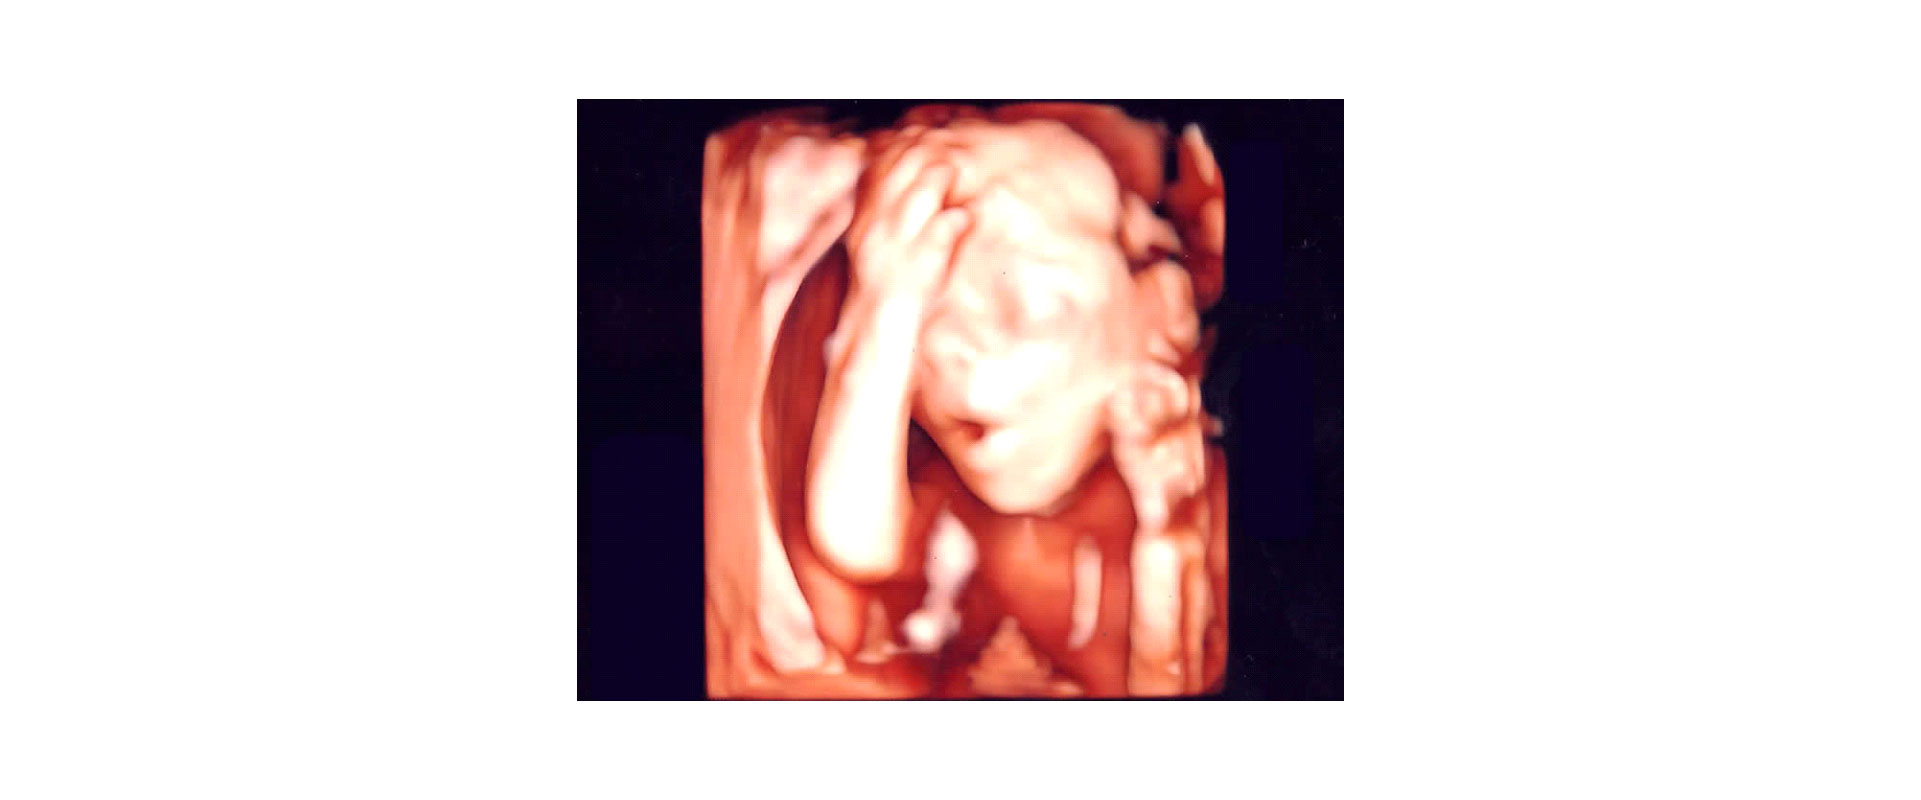

⦁ πιο «πραγματικές» εικόνες του εμβρύου στο φυσικό του περιβάλλον

Στο ιατρείο μας χρησιμοποιούμε μηχάνημα υπερήχων τελευταίας τεχνολογίας έτσι ώστε να έχουμε ακίνητη τρισδιάστατη απεικόνιση του εμβρύου (3D) και της μήτρας ή να βλέπουμε το έμβρυο τρισδιάστατο όπως κινείται σε πραγματικό χρόνο – real time (4D).

✓ Παρακολούθηση Εγκυμοσύνης: Λεπτομερείς εικόνες του εμβρύου για την αξιολόγηση της ανάπτυξης και της υγείας του και συμπληρωματική ανίχνευση ανωμαλιών σε συνδιασμό με το 2D υπερηχογράφημα.

Η συνηθισμένη δισδιάστατη 2D υπερηχογραφική εικόνα μας δίνει τις πιο σημαντικές πληροφορίες για το έμβρυο. Σε κάποιες σπάνιες ανωμαλίες το τρισδιάστατο υπερηχογράφημα μπορεί να μας βοηθήσει να δούμε καλύτερα ορισμένα όργανα, ωστόσο είναι το δισδιάστατο υπερηχογράφημα που βασικά θα μας κατευθύνει στη διάγνωσή μας. Έτσι, πιθανόν και να αυξάνεται η ακρίβεια της διάγνωσης, και παράλληλα, γίνεται πιο κατανοητή και από τους γονείς.

⦁ Ένα υπερηχογράφημα 3D/ 4D μπορεί να πραγματοποιηθεί οποιαδήποτε στιγμή της εγκυμοσύνης αρκεί η θέση του μωρού να είναι ευνοϊκή. Είναι σύνηθες να εκτελείται μεταξύ 20ης – 34ης εβδομάδας της κύησης. Τα καλύτερα αποτελέσματα λαμβάνονται αν το υπερηχογράφημα πραγματοποιηθεί μεταξύ 27ης – 32ης εβδομάδας γιατί τότε η αναλογία διαστάσεων του μωρού προς την ποσότητα του αμνιακού υγρού είναι η καταλληλότερη.